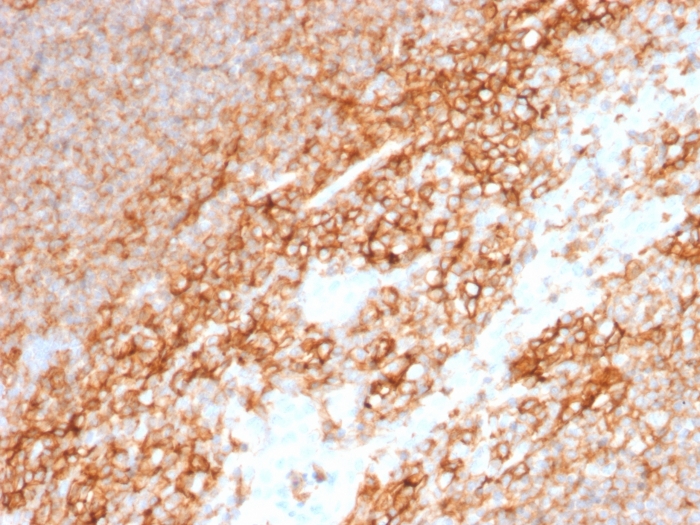

Immunohistochemistry (IHC)

1-2ug/ml

30 min at RT. Staining of formalin-fixed tissues requires heating tissue sections in 10mM Tris with 1mM EDTA, pH 9.0, for 45 min at 95°C followed by cooling at RT for 20 minutes

Recognizes a cell surface glycoprotein of 80-95kDa (CD44) on lymphocytes, monocytes, and granulocytes (Leucocyte Typing Workshop V). Its epitope is resistant to digestion by trypsin and chymotrypsin. This MAb selectively interferes with lymphocyte binding to lymph node, mucosal and synovial endothelium. The CD44 family of glycoproteins exists in a number of variant isoforms, the most common being the standard 85-95kDa or hematopoietic variant (CD44s). Higher molecular weight isoforms are described in epithelial cells (CD44v), which are believed to function in intercellular adhesion and stromal binding. CD44 immunostaining is commonly used for the discrimination of urothelial transitional cell carcinoma in-situ from non-neoplastic changes in the urothelium.

HeLa cells. Paracortex in tonsil or lymph node.